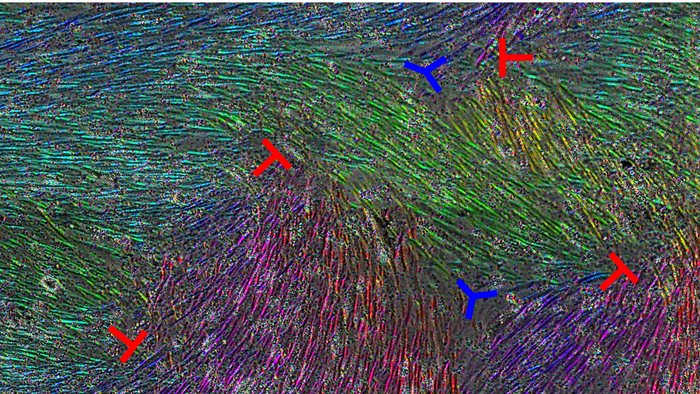

In APL Bioengineering, by AIP Publishing, biophysics researchers at the University of Wisconsin explain how microscopic defects in how healthy cells line up can alter how easily ovarian cancer cells invade tissue. Using an experimental model, where the cellular makeup mimics the lining of the abdominal cavity, the group found that disruptions in the normal cellular layout, called topological defects, affect the rate of tumor cell invasion.

Such elongation led to areas of well-ordered cell layers and left other areas with alignment imperfections, causing the topological defects. These flaws in this alignment have been associated with a host of microscopic influences, including altered cell density, motion, and forces.

The patterns of cell flow were different near the defects, with certain defects causing inward cell flow, toward the center of the defect. At those locations of inward flow, the cancer cells passed through the mesothelial barrier more slowly.